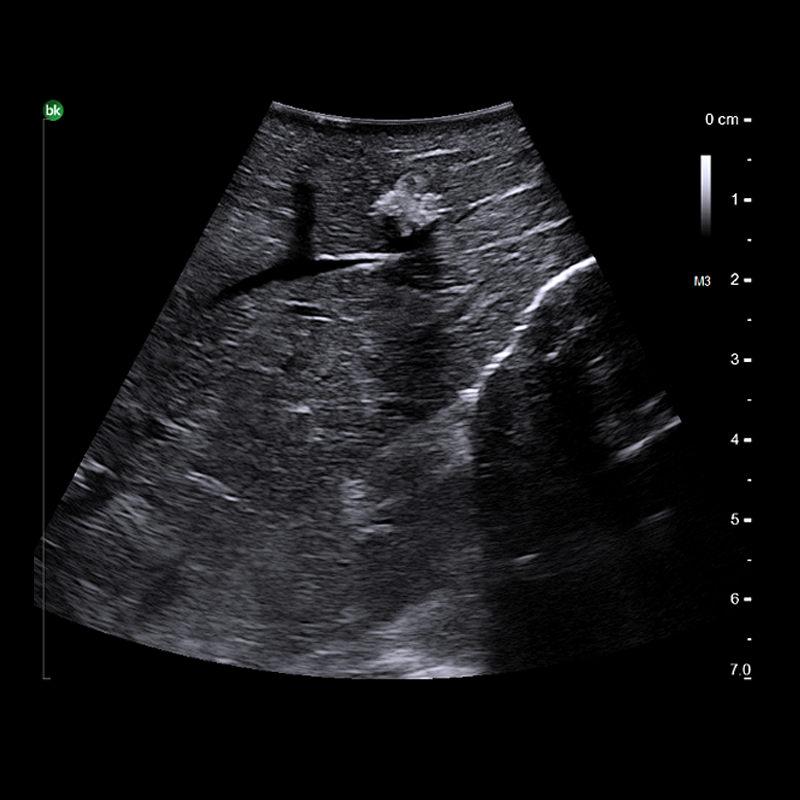

Hyperechoic Metastatic Liver Lesion with Acoustic Shadowing